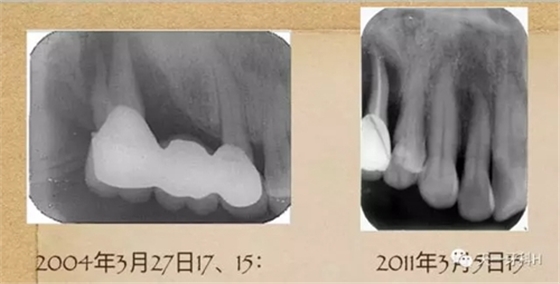

2004年3月27日17:

17牙槽骨已經(jīng)破壞到了根尖,這樣的牙齒的松動度已經(jīng)到達了三度,17的每一次搖動都會造成固定橋另一端的基牙15的搖動,久而久之15的牙槽骨也被破壞了,此時應該盡早拆除固定橋。

2011年3月3日拍攝:

15 的牙槽骨破壞已經(jīng)到達根尖,這樣的牙齒就是無法保留的牙齒,只能拔掉?;仡^看2004年的15,盡管有牙周膜間隙的改變,如果當時患者聽從勸導,拆除烤瓷橋保住15號牙是毫無懸念的。我不知道這個病例的發(fā)生、發(fā)展過程

能否讓你們醒悟,牙周病患者做烤瓷牙要慎之又慎!

2011年3月5日:15三度松動,局麻下拔出。